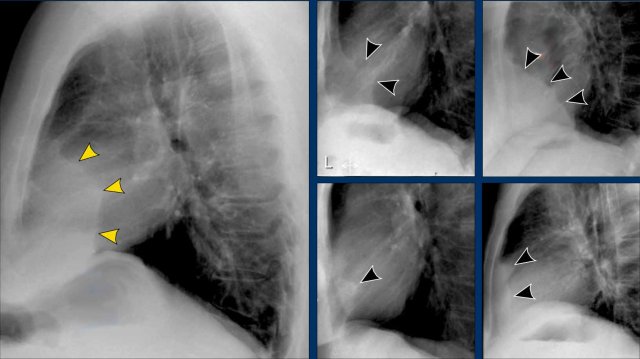

Displacement of the Azygoesophageal Line (1) – Hiatal hernia

A hiatal hernia (arrowheads) is the most common cause of displacement of the azygoesophageal line as seen on the PA-view.

Notice the air within the hernia on the lateral view (black arrow).